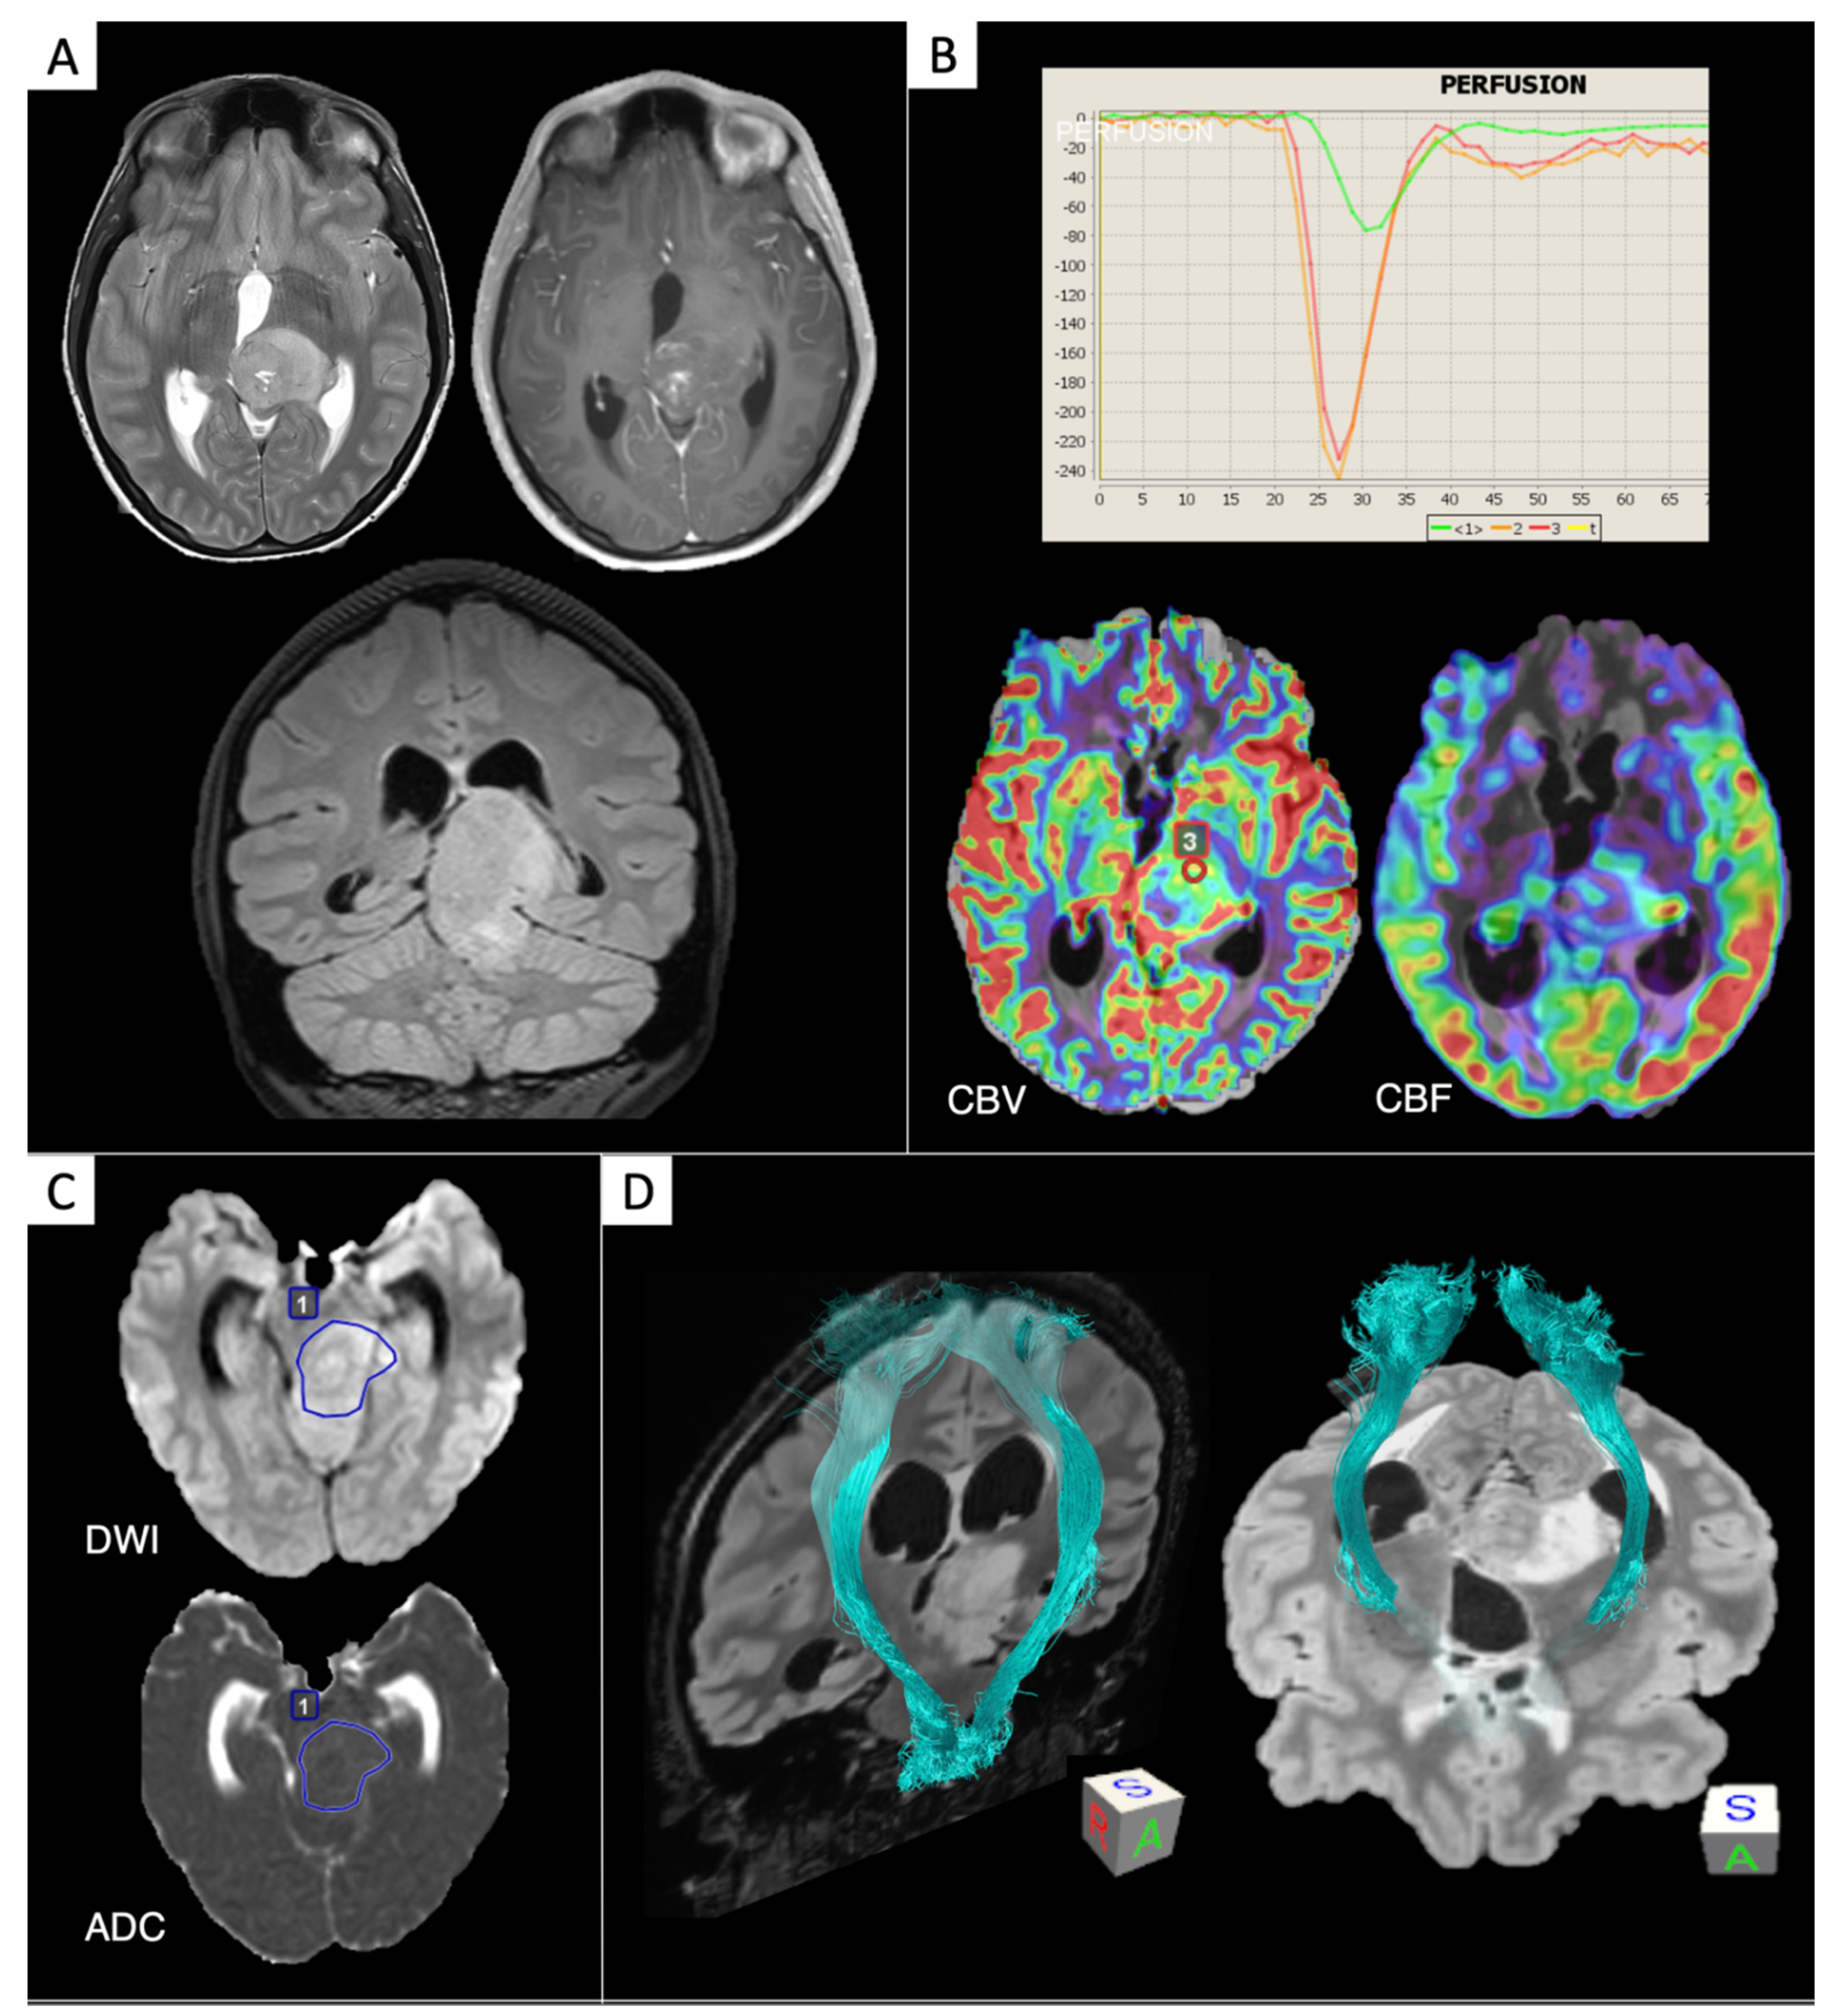

5. Additional Molecular Markers in GBM: Epidermal Growth Factor Receptor (EGFR) Modifications and O6-Methylguanine DNA Methyltransferase (MGMT) Methylation

7. Diffuse Midline Gliomas H3K27M-Mutated

- Park, Y.W.; Ahn, S.; Park, C.J.; Han, K.; Kim, E.H.; Kang, S.-G.; Chang, J.H.; Kim, S.H.; Lee, S.-K. Diffusion and perfusion MRI may predict EGFR amplification and the TERT promoter mutation status of IDH-wildtype lower-grade gliomas. Eur. Radiol. 2020, 1. [Google Scholar] [CrossRef]

- Qiu, T.; Chanchotisatien, A.; Qin, Z.; Wu, J.; Du, Z.; Zhang, X.; Gong, F.; Yao, Z.; Chu, S. Imaging characteristics of adult H3 K27M-mutant gliomas. J. Neurosurg. 2019, 133, 1662–1670. [Google Scholar] [CrossRef] [PubMed]

- Aboian, M.S.; Solomon, D.A.; Felton, E.; Mabray, M.C.; Villanueva-Meyer, J.E.; Mueller, S.; Cha, S. Imaging characteristics of pediatric diffuse midline gliomas with histone H3 K27M mutation. Am. J. Neuroradiol. 2017, 38, 795–800. [Google Scholar] [CrossRef] [PubMed]

- Piccardo, A.; Tortora, D.; Mascelli, S.; Severino, M.; Piatelli, G.; Consales, A.; Pescetto, M.; Biassoni, V.; Schiavello, E.; Massollo, M.; et al. Advanced MR imaging and 18F-DOPA PET characteristics of H3K27M-mutant and wild-type pediatric diffuse midline gliomas. Eur. J. Nucl. Med. Mol. Imaging 2019, 46, 1685–1694. [Google Scholar] [CrossRef]

- Chen, H.; Hu, W.; He, H.; Yang, Y.; Wen, G.; Lv, X. Noninvasive assessment of H3 K27M mutational status in diffuse midline gliomas by using apparent diffusion coefficient measurements. Eur. J. Radiol. 2019, 114, 152–159. [Google Scholar] [CrossRef]

- Jaimes, C.; Vajapeyam, S.; Brown, D.; Kao, P.-C.; Ma, C.; Greenspan, L.; Gupta, N.; Goumnerova, L.; Bandopadhayay, P.; Dubois, F.; et al. MR Imaging correlates for molecular and mutational analyses in children with diffuse intrinsic pontine glioma. Am. J. Neuroradiol. 2020, 41, 874–881. [Google Scholar] [CrossRef]

- Hales, P.W.; D’Arco, F.; Cooper, J.; Pfeuffer, J.; Hargrave, D.; Mankad, K.; Clark, C. Arterial spin labelling and diffusion-weighted imaging in paediatric brain tumours. NeuroImage Clin. 2019, 22, 101696. [Google Scholar] [CrossRef]